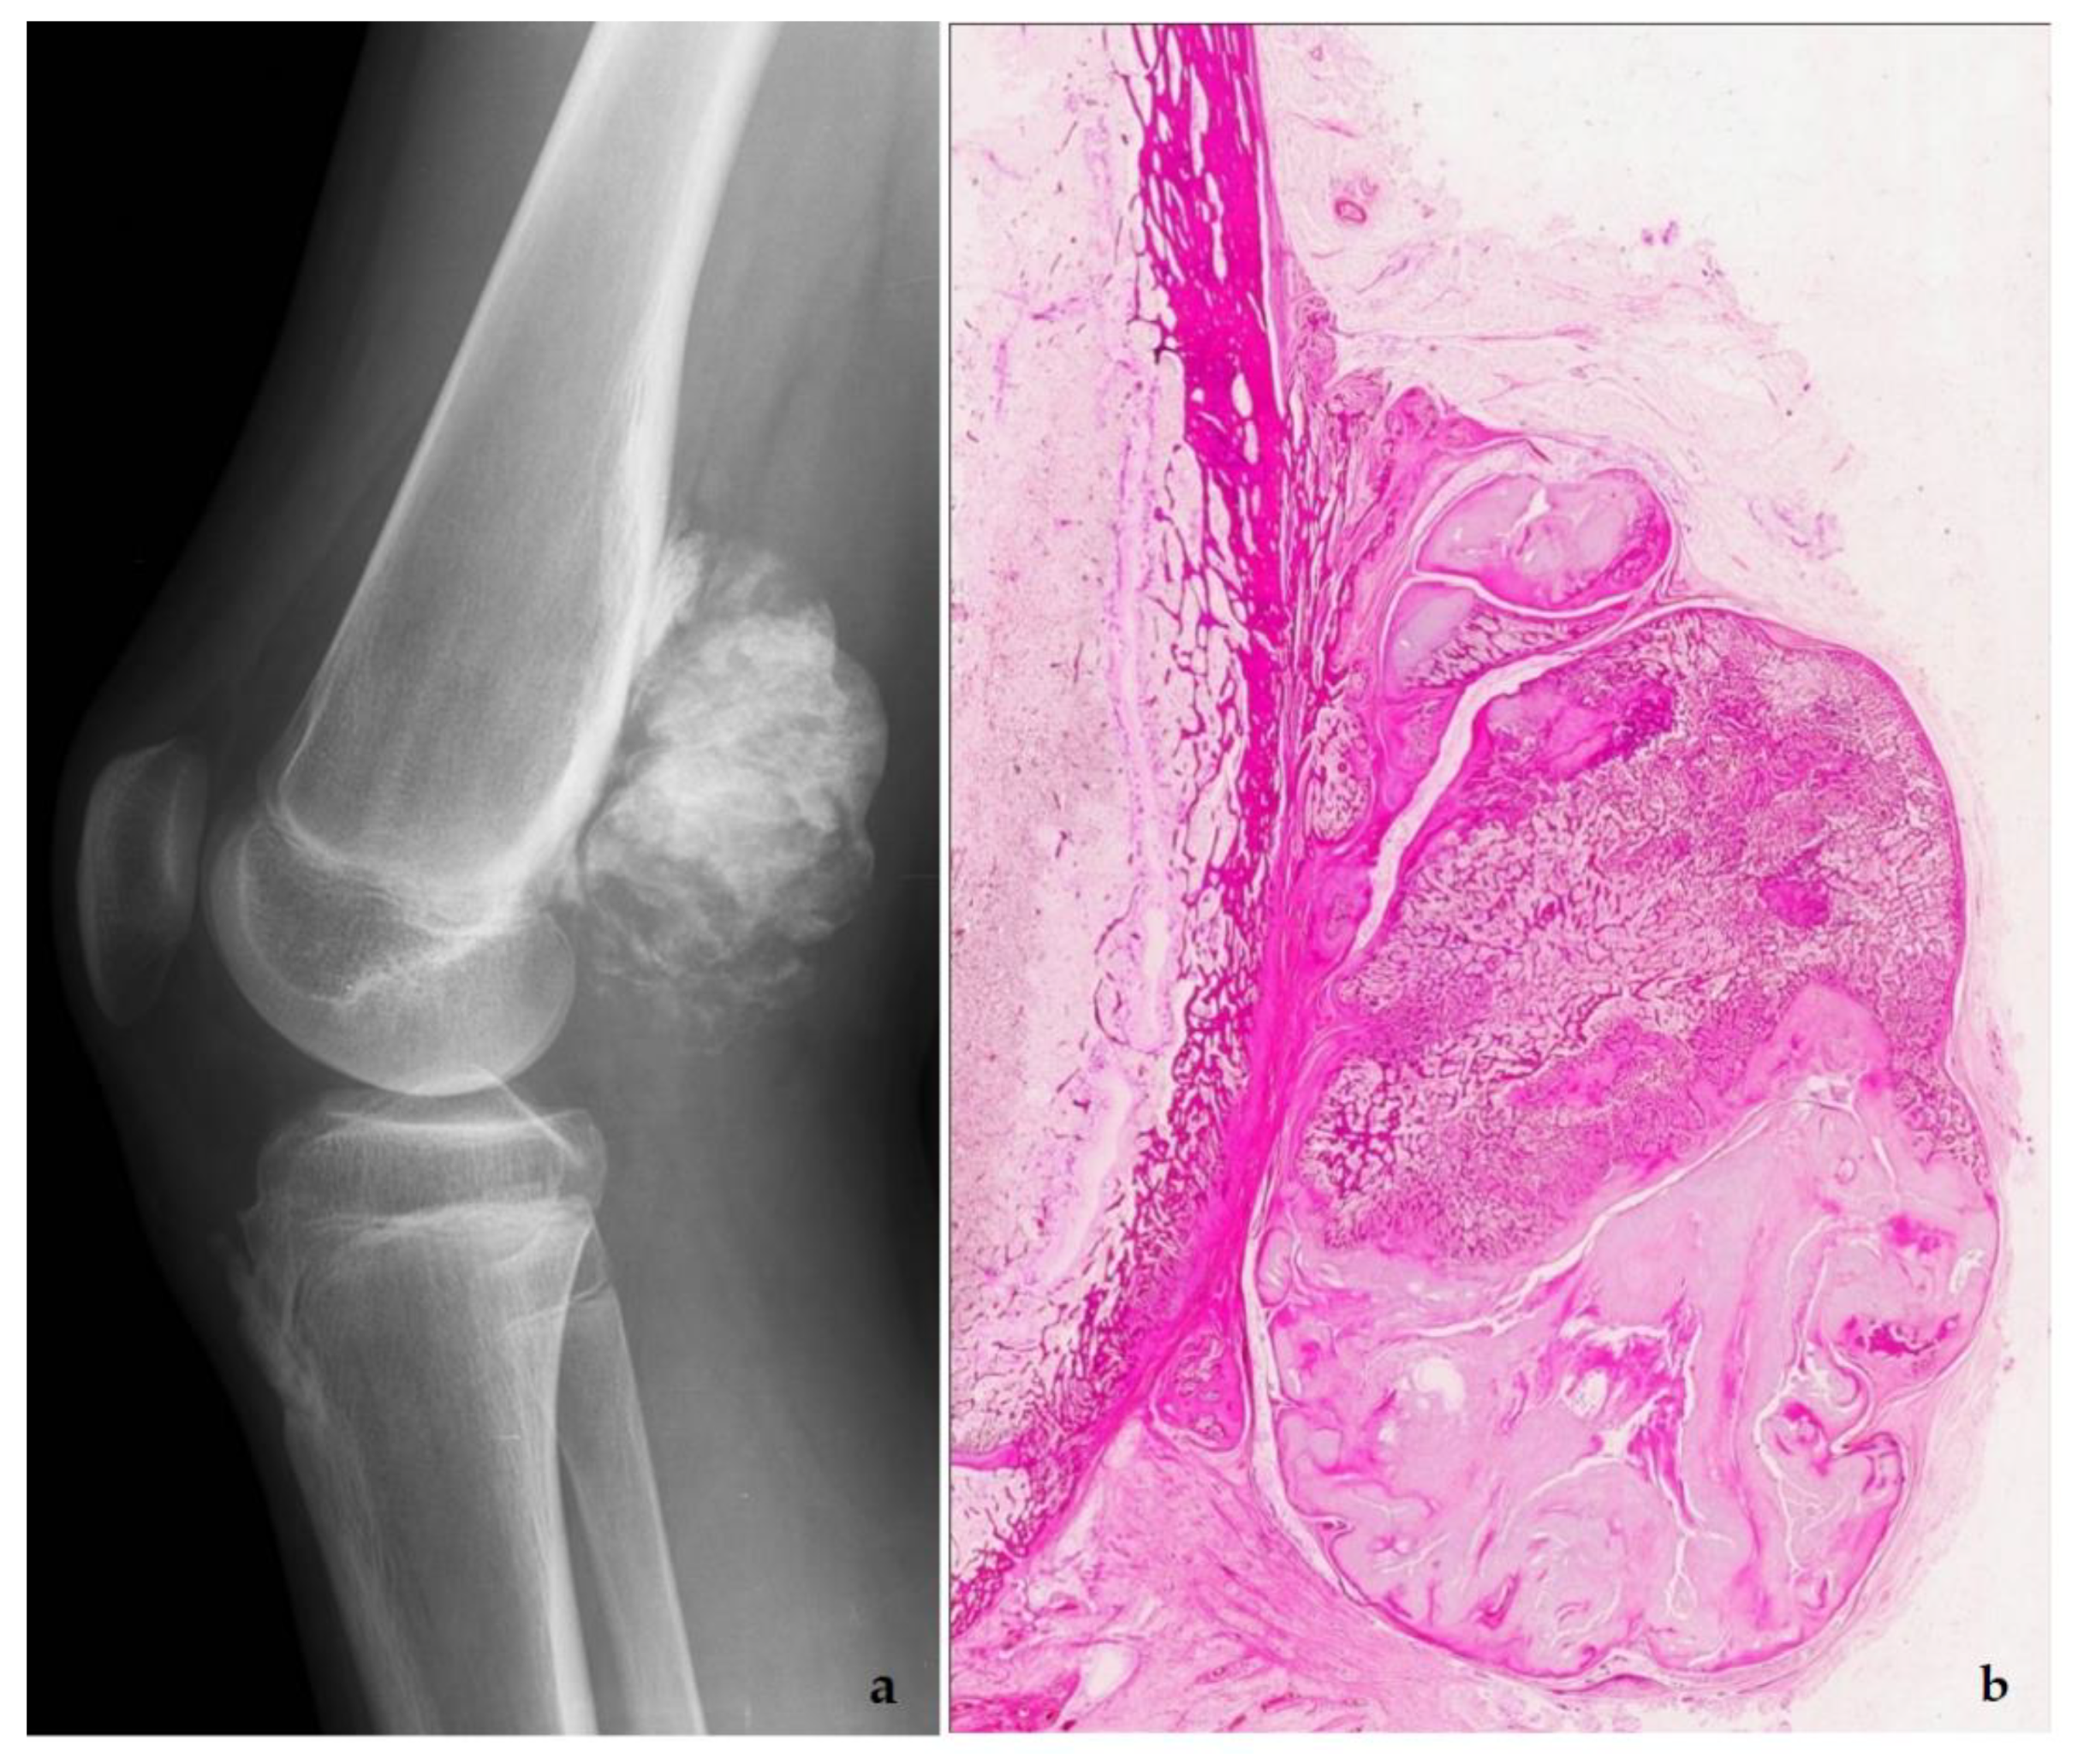

5. Low-Grade Osteosarcoma

- Wang, J.; Nord, K.H.; O’Donnell, P.G.; Yoshida, A. Parosteal osteosarcoma. In WHO Classification of Tumours Editorial Board. Soft Tissue and Bone Tumors; International Agency for Research on Cancer: Lyon, France, 2020; pp. 410–413. [Google Scholar]

- Yoshida, A.; Bredella, M.A.; Gambarotti, M.; Sumathi, V.P. Low-grade central osteosarcoma. In WHO Classification of Tumours Editorial Board. Soft Tissue and Bone Tumors; International Agency for Research on Cancer: Lyon, France, 2020; pp. 400–402. [Google Scholar]

- Dujardin, F.; Bui Nhuyen Binh, M.; Bouvier, C.; Gomez-Brouchet, A.; Larousserie, F.; de Muret, A.; Louis-Brennetot, C.; Aurias, A.; Coindre, J.M.; Guillou, L.; et al. MDM2 and CDK4 immunohistochemistry is a valuable tool in the differential diagnosis of low-grade osteosarcomas and other primary fibro-osseous lesions of the bone. Mod. Pathol. 2011, 24, 624–637. [Google Scholar] [CrossRef] [PubMed]

- Yoshida, A.; Ushiku, T.; Motoi, T.; Beppu, Y.; Fukayama, M.; Tsuda, H.; Shibata, T. MDM2 and CDK4 Immunohistochemical Coexpression in High-grade Osteosarcoma: Correlation with a Dedifferentiated Subtype. Am. J. Surg. Pathol. 2012, 36, 423–431. [Google Scholar] [CrossRef] [PubMed]